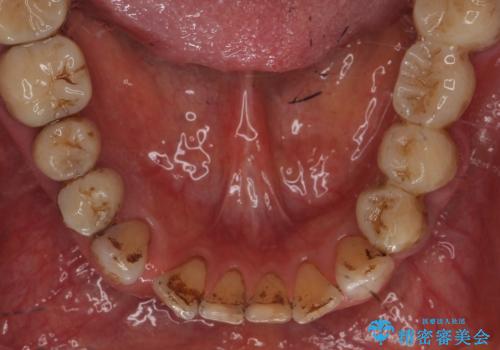

- 日頃からコーヒーをよく飲むそうでべったりとステインが付着していました。

ステインがたくさん付着していたので、エアフローを用いてステインを除去しました。そのため、直後の写真は歯肉からの出血が見られます。

まず歯石取りを行い歯肉の状態を改善後、後日PMTC30分コースをしました。